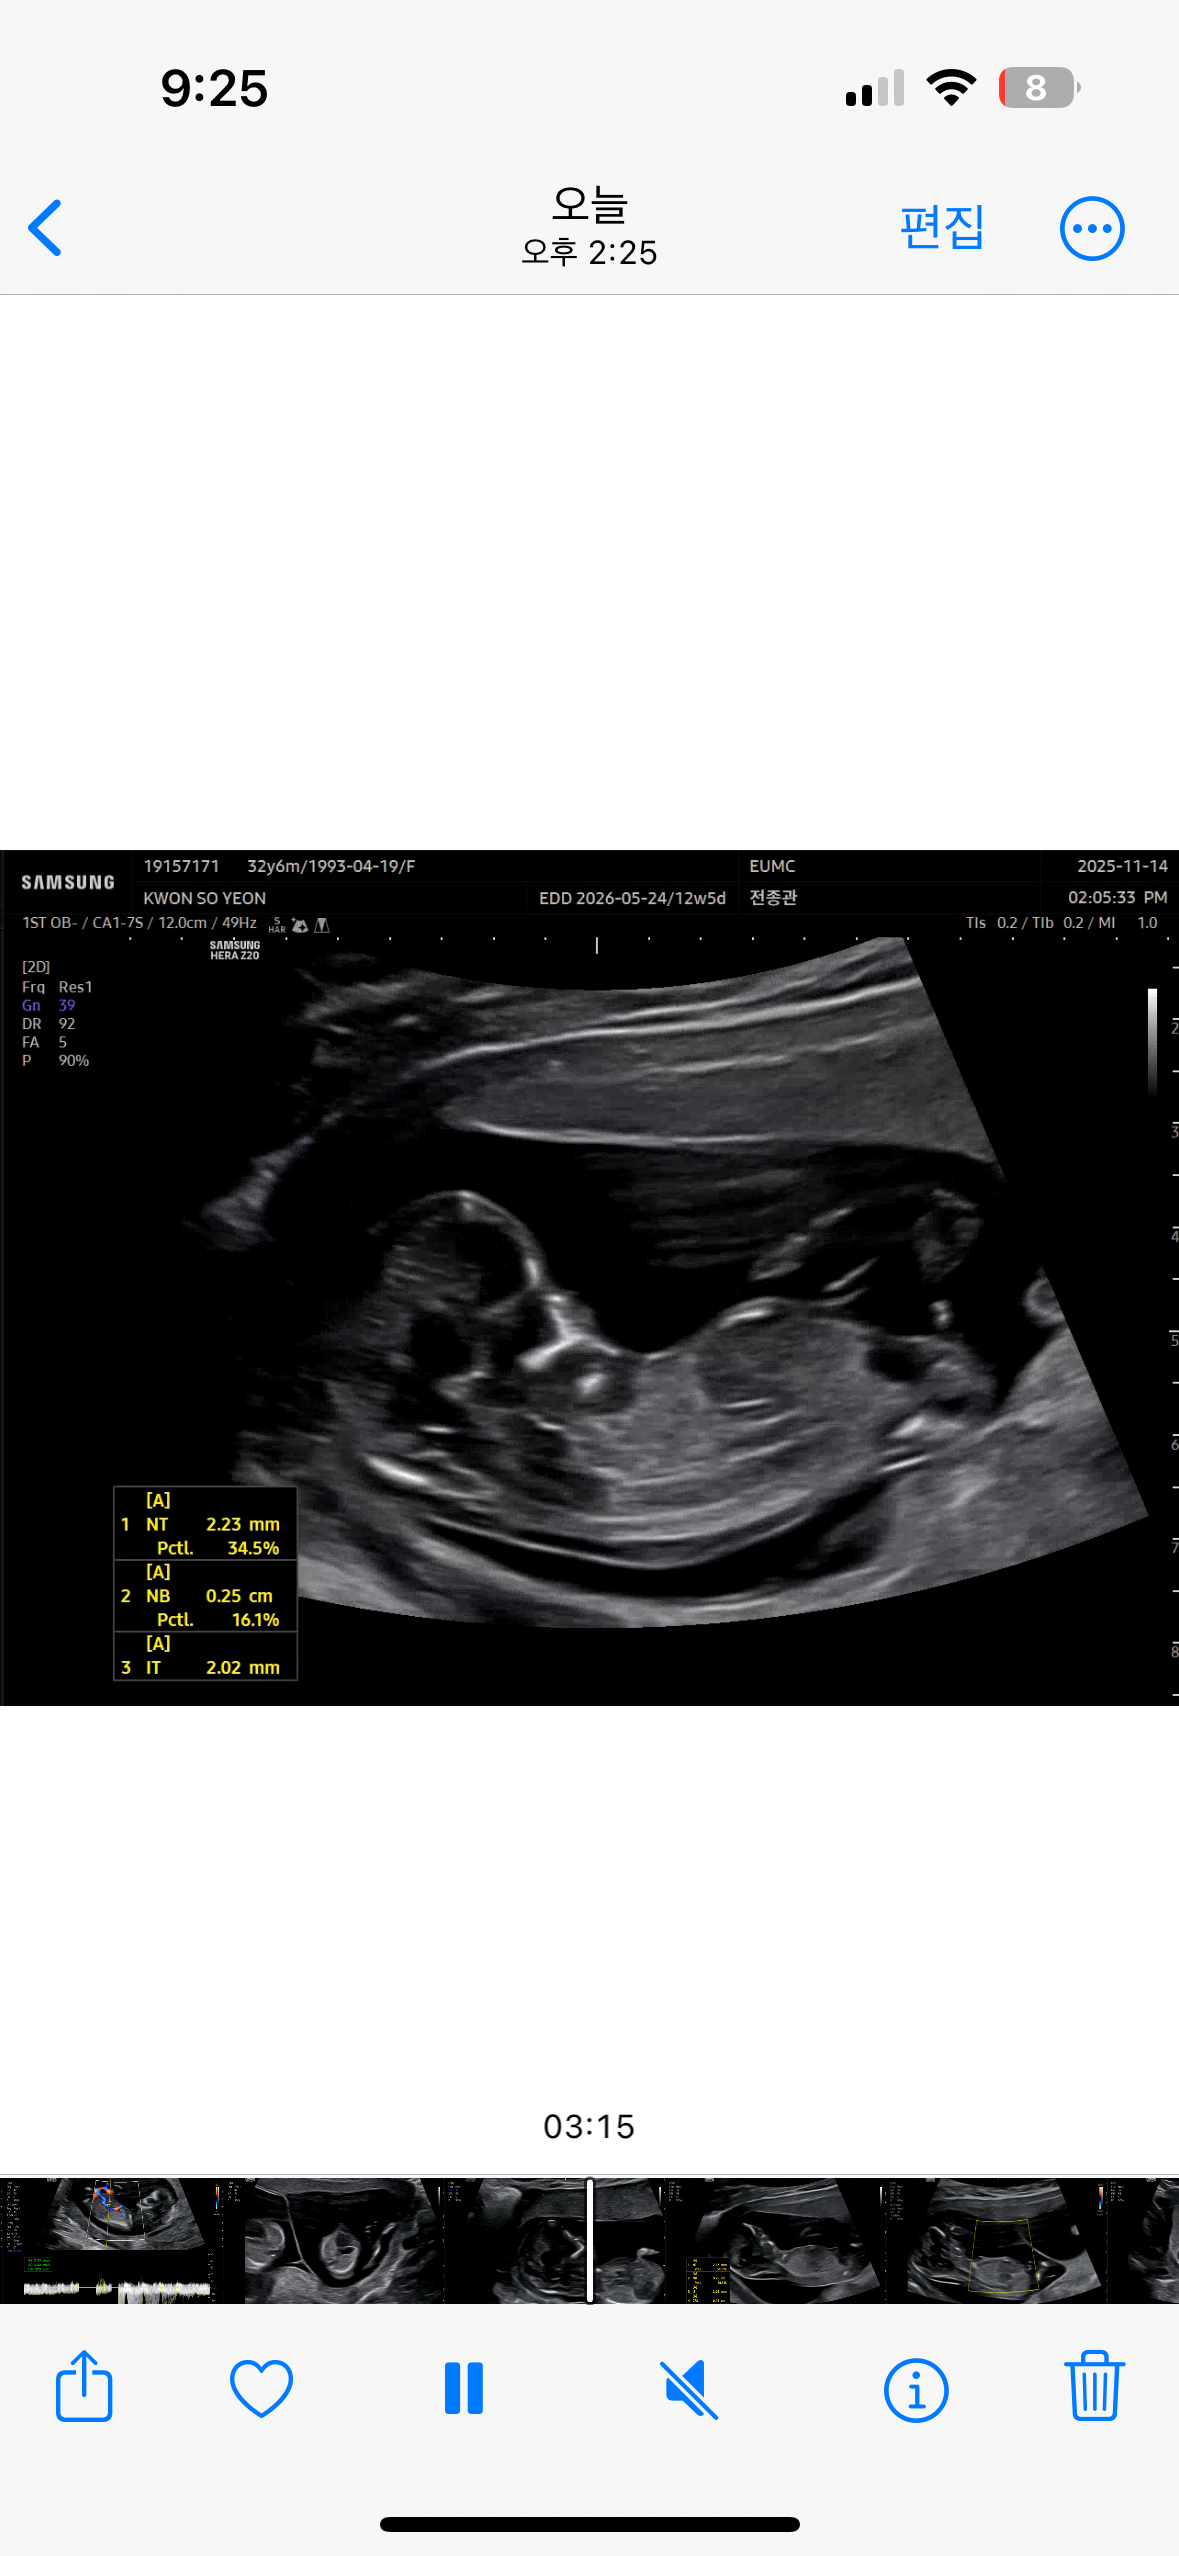

각도법!!12주5일차 제발 알려주세요 고수님들!

12주차인제 제발 좀 부탁드러요 ㅠㅠ